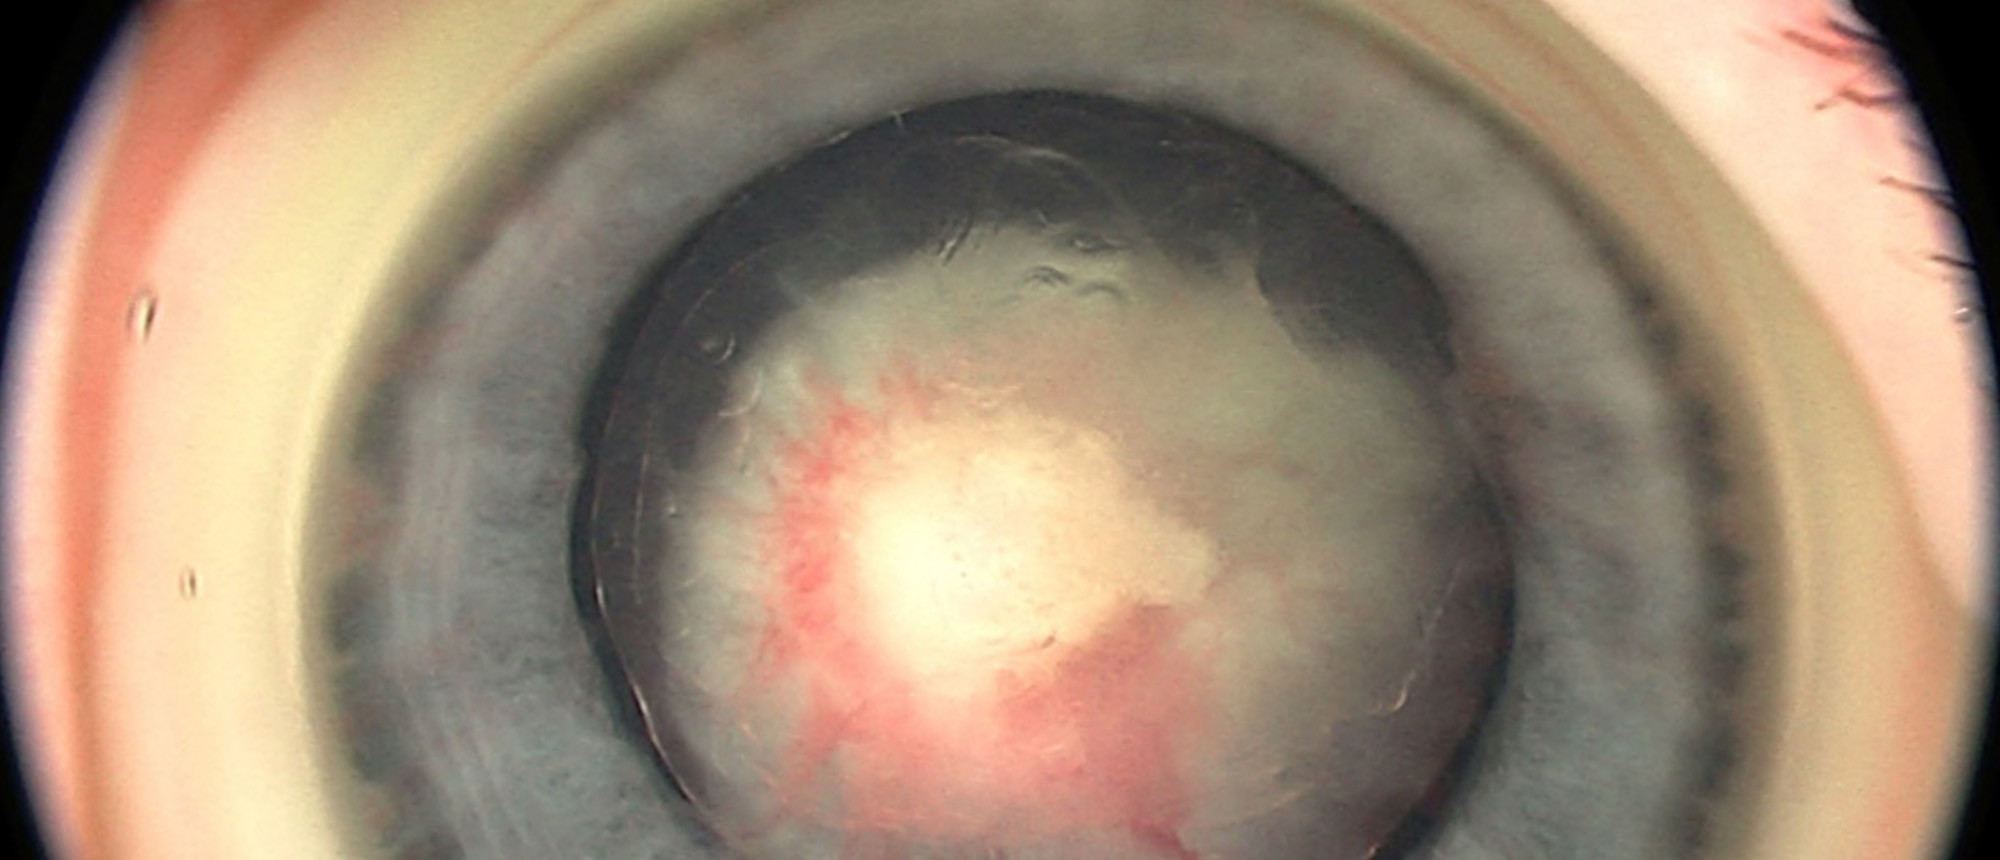

Persistent Fetal Vasculature

Persistent Fetal Vasculature This patient with past ocular history of leukocoria was referred forretinal evaluation. Ophthalmological evaluation under anesthesia was notable for a cataractous lens with spherical appearance,anterior segment dysplasia andpersistence of the iridohyaloid vessels and tu…